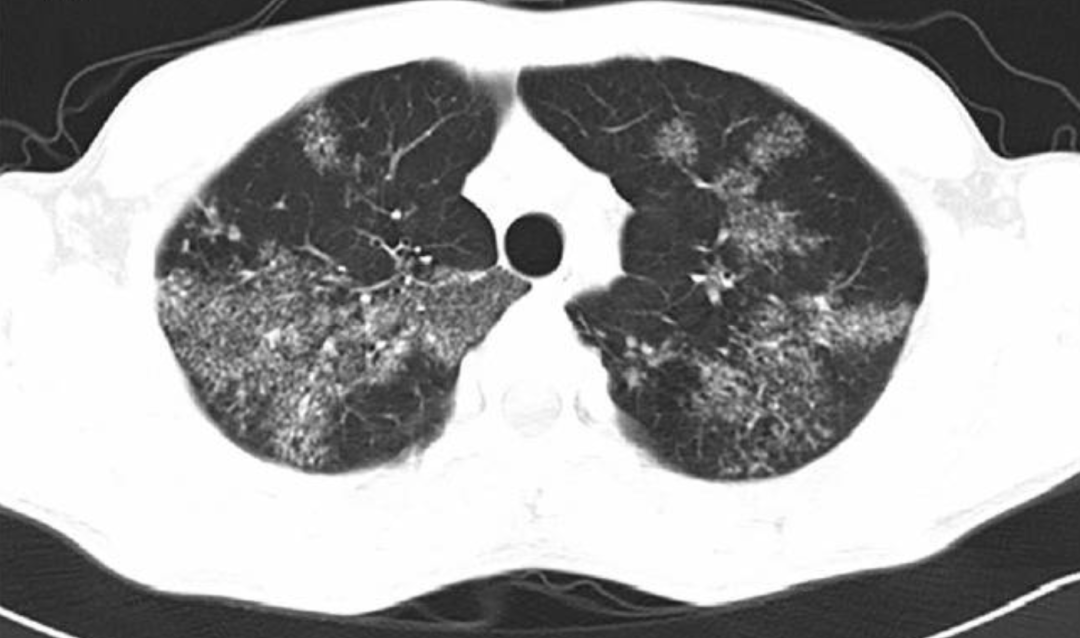

一位19岁女性,有缺铁性贫血史。间断腹痛半年,近3月消瘦10kg,上腹痛伴发热盗汗、干咳1周。胸片及肺CT可见双肺弥漫小结节影,部分融合倾向。3次诱导痰均抗酸菌阳性。[7]

影像中可见斑片结节状的病变相对均匀地弥漫分布于双肺。如果说是沿着气道,又没有明显的树芽症表现,如果说是血行播散,这些病变比一般的粟粒性肺结核又显然粗大的多。所以这个影像是非常特别,有些像转移瘤。但仔细看这些斑片结节几乎都不与胸膜接触,同时其边缘并不清晰光滑而是呈开花状,提示它的本质很可能是小叶中心性结节。